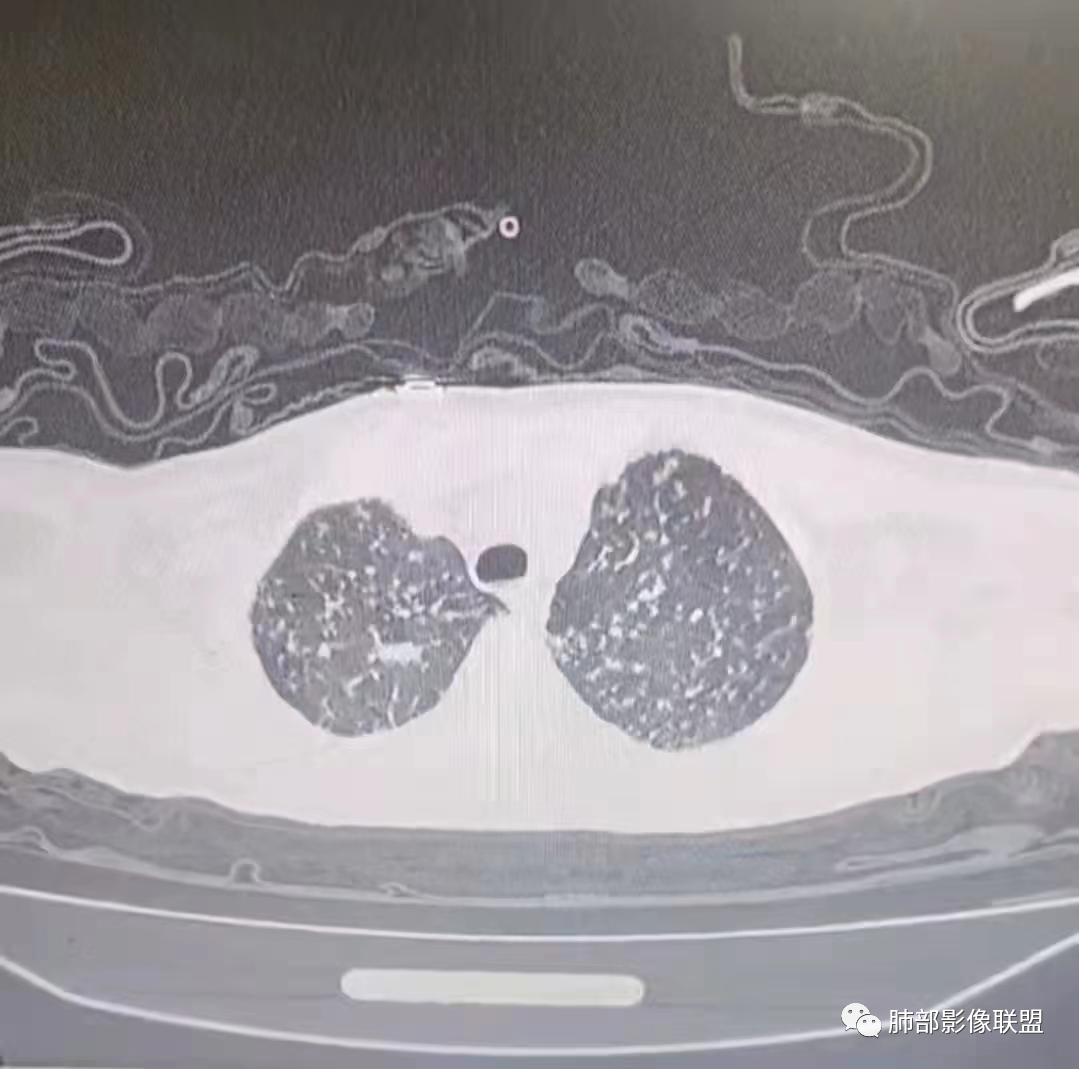

1、临床特点:21岁男性,两天以前受凉后出现咳嗽,无明显咳痰,没有发热,有左胸痛,化验白细胞不高,降钙素原升高。C反应蛋白明显增高,结核抗体阴性。

2、影像特点:右肺中叶、左肺下舌段可见支扩。左肺下舌段及两肺下叶可见片状实变影及发结节影,病灶边界多显示不清,纵隔窗显示病灶密度较均匀,未见液化、空洞或钙化。左肺下叶部分病灶沿支气管分布,并可见局部支气管管壁增厚。

kartagener综合症(属原发性纤毛不活动,主要包括内脏反位、支扩、鼻窦炎等)